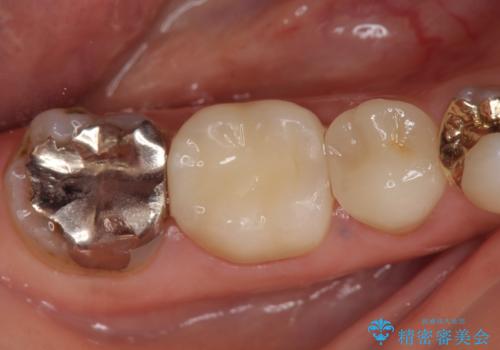

診査の結果右下6の歯の神経が死んでいたため根管治療を行い、オールセラミッククラウンによる補綴を行いました。

今回用いたオールセラミッククラウンはジルコニアフレームという白い素材の上にセラミックを盛っているため、審美性が非常に高いのが特徴です。

また、ジルコニアは人工ダイヤモンドの材料にも使われているほど高い強度を持っており、そのためオールセラミッククラウンは審美性だけでなく、奥歯やブリッジの補綴も可能とするクラウンです。